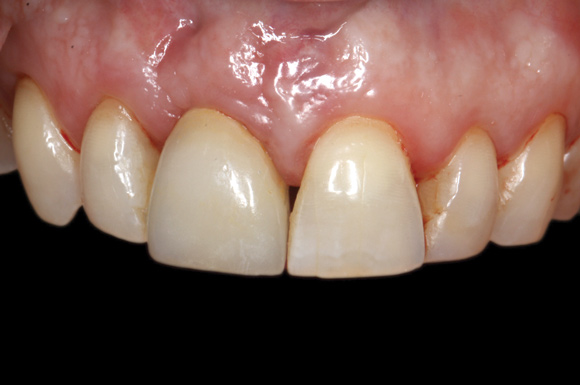

4. Facial and occlusal views of initial clinical presentation of tooth No. 8.

Figure 4

5. Facial and occlusal views of initial clinical presentation of tooth No. 8.

Figure 5

A 56-year-old female patient was referred for the evaluation of tooth No. 8 (Figure 4 and Figure 5). A periapical radiograph indicated that the tooth had undergone apicoectomy and received an excessively long post (Figure 6), and a cone-beam computed tomography (CBCT) scan of the site revealed a lack of buccal plate bone (Figure 7).

Esthetic implant placement was selected as the preferred treatment modality to restore function, preserve the smile, and provide a psychologic benefit. In addition to performing a complete periodontal evaluation, including periodontal probing, localization of the gingival margin, and calculation of the clinical attachment level, it was necessary to quantify the amount of keratinized tissue and gingival thickness for diagnosis and treatment planning. This patient was diagnosed with localized periodontitis (Stage II, Grade B) as well as other conditions affecting the periodontium, including an endodontic-periodontal lesion and gingival recession.26